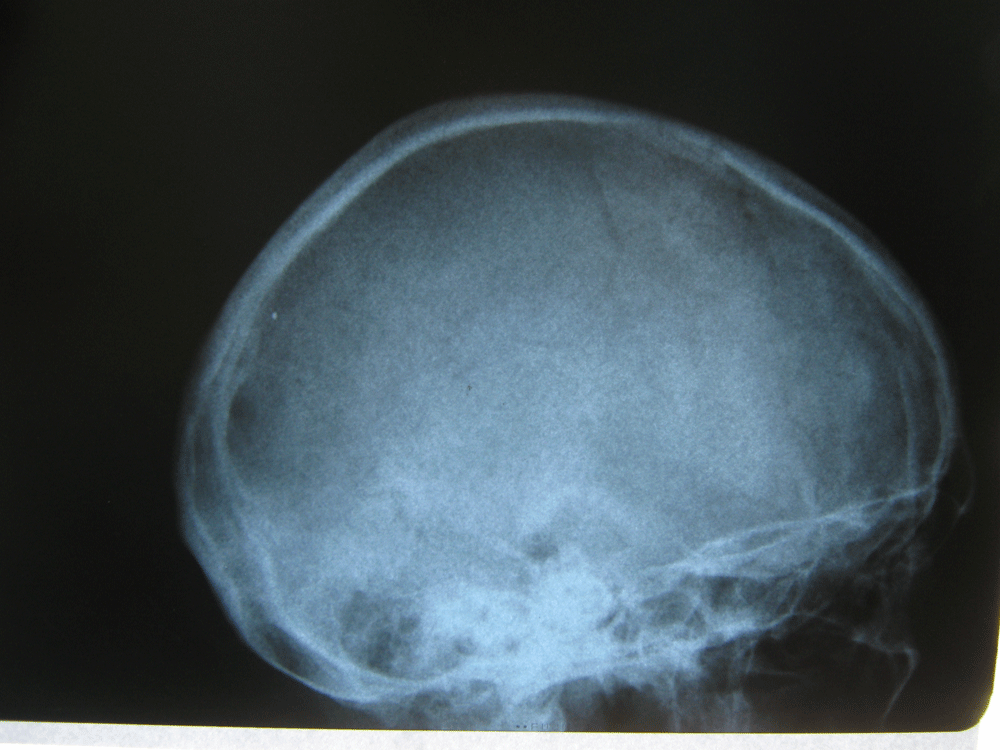

Здравствуйте! Меня сбил автомобиль. Бригада скорой помощи доставила меня в стационар с диагнозом - сотрясение мозга, ушиб грудного отдела позвоночника, компрессионный перелом грудного отдела позвоночника. При поступлении в стационар мне было сделано несколько рентгеновских снимков и поставлен диагноз - компрессионный перелом 4 грудного позвонка. Из-за "мутных" рентгеновских снимков через 9 дней мне сделали КТ и диагноз сняли на основании этого заключения.Судебная медицина - Прикрепленное изображение Мне сказали что перелом шейного позвонка у меня старый и поменяли диагноз - ушиб верхне-грудного отдела позвоночника, болевой синдром. По запросу я получила копию записи КТ. Всю запись КТ выложить не могу, т.к. не могу убрать фамилию. Выкладываю некоторые снимки: Судебная медицина - Прикрепленное изображение Судебная медицина - Прикрепленное изображение Судебная медицина - Прикрепленное изображение Судебная медицина - Прикрепленное изображение Судебная медицина - Прикрепленное изображение Судебная медицина - Прикрепленное изображение Судебная медицина - Прикрепленное изображение Действительно ли по этим снимкам можно сказать, что перелом шейного позвонка "старый"? Правильно ли описание КТ? Я не эксперт, но по-моему 5 грудной позвонок тоже поврежден. Можно ли оспорить заключение врача делавшего КТ? Если можно, то как это сделать? Ведь речь идет об установлении причинно-следственной связи между ДТП и травмой, а до ДТП у меня никаких травм позвоночника не было. Может рентгеновские снимки тоже о чем то скажут.Судебная медицина - Прикрепленное изображениеСудебная медицина - Прикрепленное изображениеСудебная медицина - Прикрепленное изображение

Для этого надо исследовать все сканы. Желательно - с 3D-реформацией изображения. С внимательным анализом костной структуры на уровне дефекта (есть ли признаки отека костной ткани в его зоне, наличие реакции мягких тканей, состояние краев фрагментов и т.д.). Получите все сканы КТ на диске или на флешке (они должны храниться в архиве КТ). И проконсультируйте их у высококвалифицированного специалиста по КТ и/или в любом крупном Бюро судебно-медицинской экспертизе, в штате которого есть эксперт-рентгенолог. Возможно, понадобится сделать контрольное КТ исследование с целью обнаружения динамики выявленных изменений (впрочем, вопрос об этом будет решен после ознакомления рентгенолога с КТ, т.к., возможно, доп.исследование не будет необходимо или же более целесообразным окажется иной вариант лучевой диагностики). По результатам консультации станет понятно, есть ли реальные основания для заявления мотивированного ходатайства о назначении дополнительной или повторной экспертизы (как это сделать - подскажет Ваш адвокат).